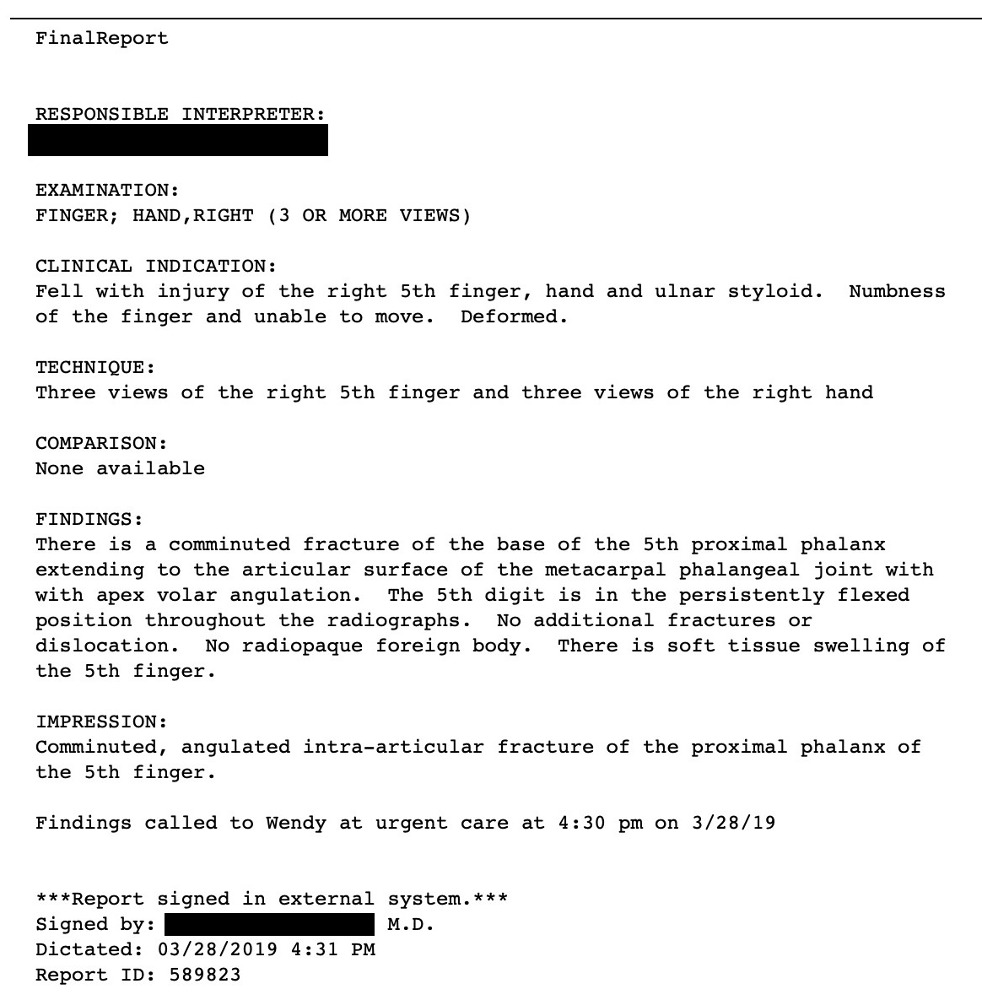

| A couple of weeks ago, I broke my Pinky! While running near the Charles river, I had fallen over a root, probably a square root. The little finger stood out a 90 degree angle. I did not need a protractor to see that this is fucked up! I went to Harvard University Services, payed my 30 dollars co-payment, was sent to x-ray and saw the doctor who looked at the finger and said: that is fucked up. You have to go the Mt Auburn emergency services! I packed my things and walked over to Mt Auburn Hospital, just happy of not having broken the third finger. Lots of people in the emergency room. Some more damaged than me. A cook told me that he had cut half has arm off and had been bleeding there for 3 hours. I payed my 30 dollars co-payment, saw the doctor who said: this is fucked up. You have to see a surgeon! They numbed up my finger and stuck it into a splint and sent me home. A couple of days later, I met the surgeon, payed the 30 dollars co-payment. The doctor looked at it and said: this is fucked up! I need more time. You have to come back later. I came back, payed my 30 dollars co-payment, and then, like a good plumber, the pieces of the finger were put together again. This was my first plumber story. Did you know that yesterday was national plumber day? Actually, national ``Hug a plumbers day"! |